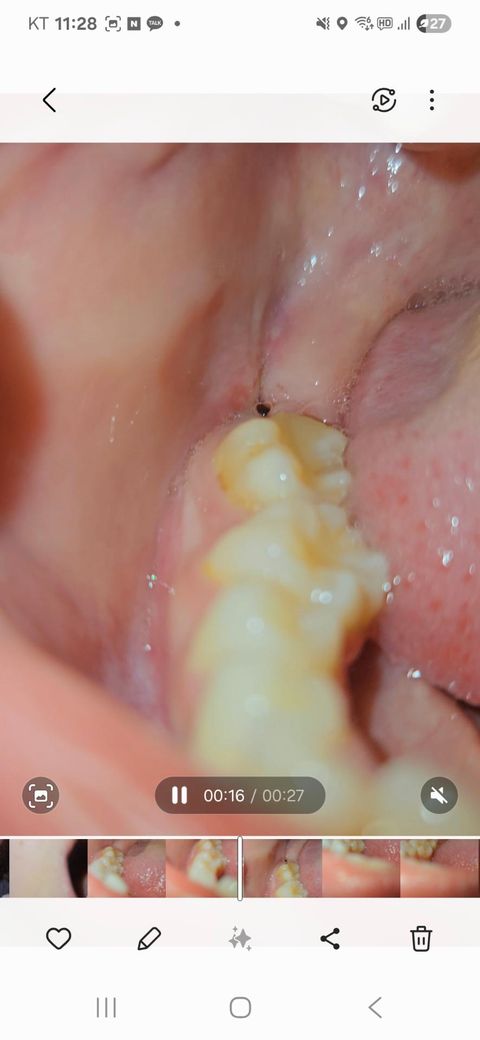

사랑니 실밥이 제거가 덜 된걸까요 구멍인걸까요???

오늘 실밥 제거 했는데 입 벌려보니 무슨 시꺼먼게 보여서 봤는데.. 이게 도저히 구멍이 맞는지... 검정색 실로 꼬맷는데 저는 아무리봐도 실밥 같거든요?... 이게 구멍인가요?.. 너무 까만데... 진짜 뭐 붙어있는거처럼 까만데요... 반대쪽은 매복에 실밥 풀고 구멍이 없었거든요.. 원래 사랑니 뽑고 이렇게 구멍이 뻥 뚫리나요..ㅠㅠㅠㅠㅠ 실밥 제가하는것도 하나도 안아팠고요ㅠㅠ 진짜 몇초만에 끝났어요.. 실밥을 다 제거를 안해주신건가요?.. 과정이 그럴수가 있나요?... 제가 암만 후레시를 비춰봐도 모르겟어요....ㅠㅠㅠ 이거 아물면 어떻게 되는거죠..

사진에 보이는건 사랑니가 잇던 공간입니다. 시간이 지나면 잇몸이 아물면서 괜찮아 지니 너무 걱정하지마세요.

사진으로 봤을 경우에는 사랑니를 발치한 부위 내부에 구멍이 있는 것으로 보입니다.

사랑니가 크거나 매복되어 있는 사랑의 경우에는 발치한 부위에 구멍이 커 보일 수 있습니다. 이런 부위는 점차 시간이 지나면서 아물게 되면 보통 3개월 정도가 걸리게 됩니다.

실밥 아니고 구멍 맞을 것 같습니다 실밥 풀고도 구멍이 좀 있을 순 있습니다 걱정안하셔도 됩니다